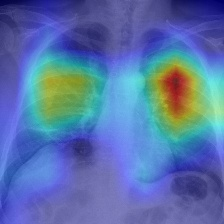

Recent epidemiological data report that worldwide more than 53 million people have been infected by SARS-CoV-2, resulting in 1.3 million deaths. The disease has been spreading very rapidly and few months after the identification of the first infected, shortage of hospital resources quickly became a problem. In this work we investigate whether chest X-ray (CXR) can be used as a possible tool for the early identification of patients at risk of severe outcome, like intensive care or death. CXR is a radiological technique that compared to computed tomography (CT) it is simpler, faster, more widespread and it induces lower radiation dose. We present a dataset including data collected from 820 patients by six Italian hospitals in spring 2020 during the first COVID-19 emergency. The dataset includes CXR images, several clinical attributes and clinical outcomes. We investigate the potential of artificial intelligence to predict the prognosis of such patients, distinguishing between severe and mild cases, thus offering a baseline reference for other researchers and practitioners. To this goal, we present three approaches that use features extracted from CXR images, either handcrafted or automatically by convolutional neuronal networks, which are then integrated with the clinical data. Exhaustive evaluation shows promising performance both in 10-fold and leave-one-centre-out cross-validation, implying that clinical data and images have the potential to provide useful information for the management of patients and hospital resources.